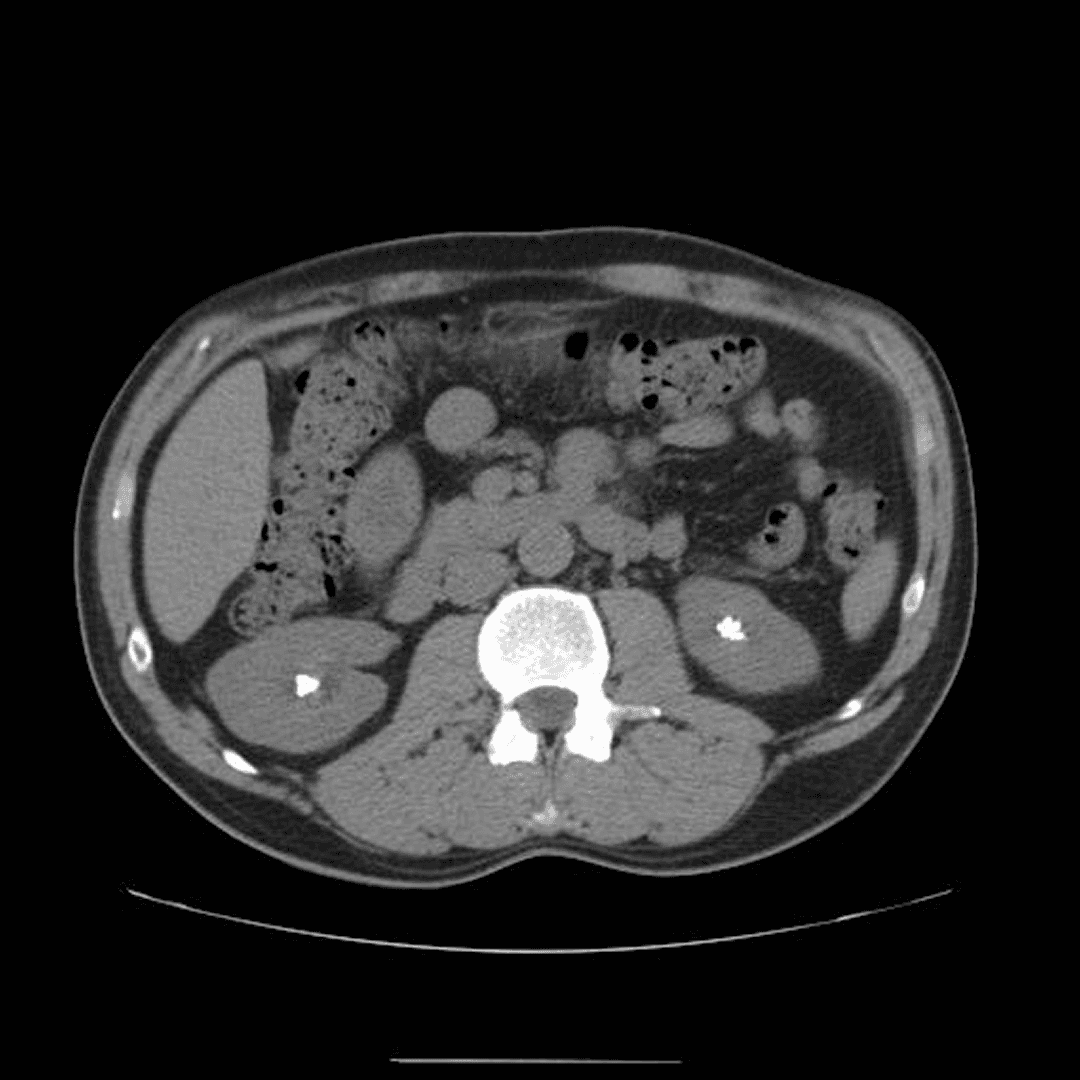

Tomografía computada de abdomen sin contraste en corte axial que muestra ambos riñones con morfología conservada y la presencia de litiasis hiperdensas localizadas en los cálices renales de manera bilateral. Los cálculos presentan una atenuación promedio de 1201 unidades Hounsfield (UH), hallazgo altamente sugestivo de composición rica en fosfato de calcio, uno de los subtipos de mayor densidad en urolitiasis. No se identifican signos de obstrucción urinaria asociados, como dilatación pielocalicial o cambios inflamatorios perirrenales, por lo que los hallazgos son compatibles con nefrolitiasis calicial bilateral no obstructiva.